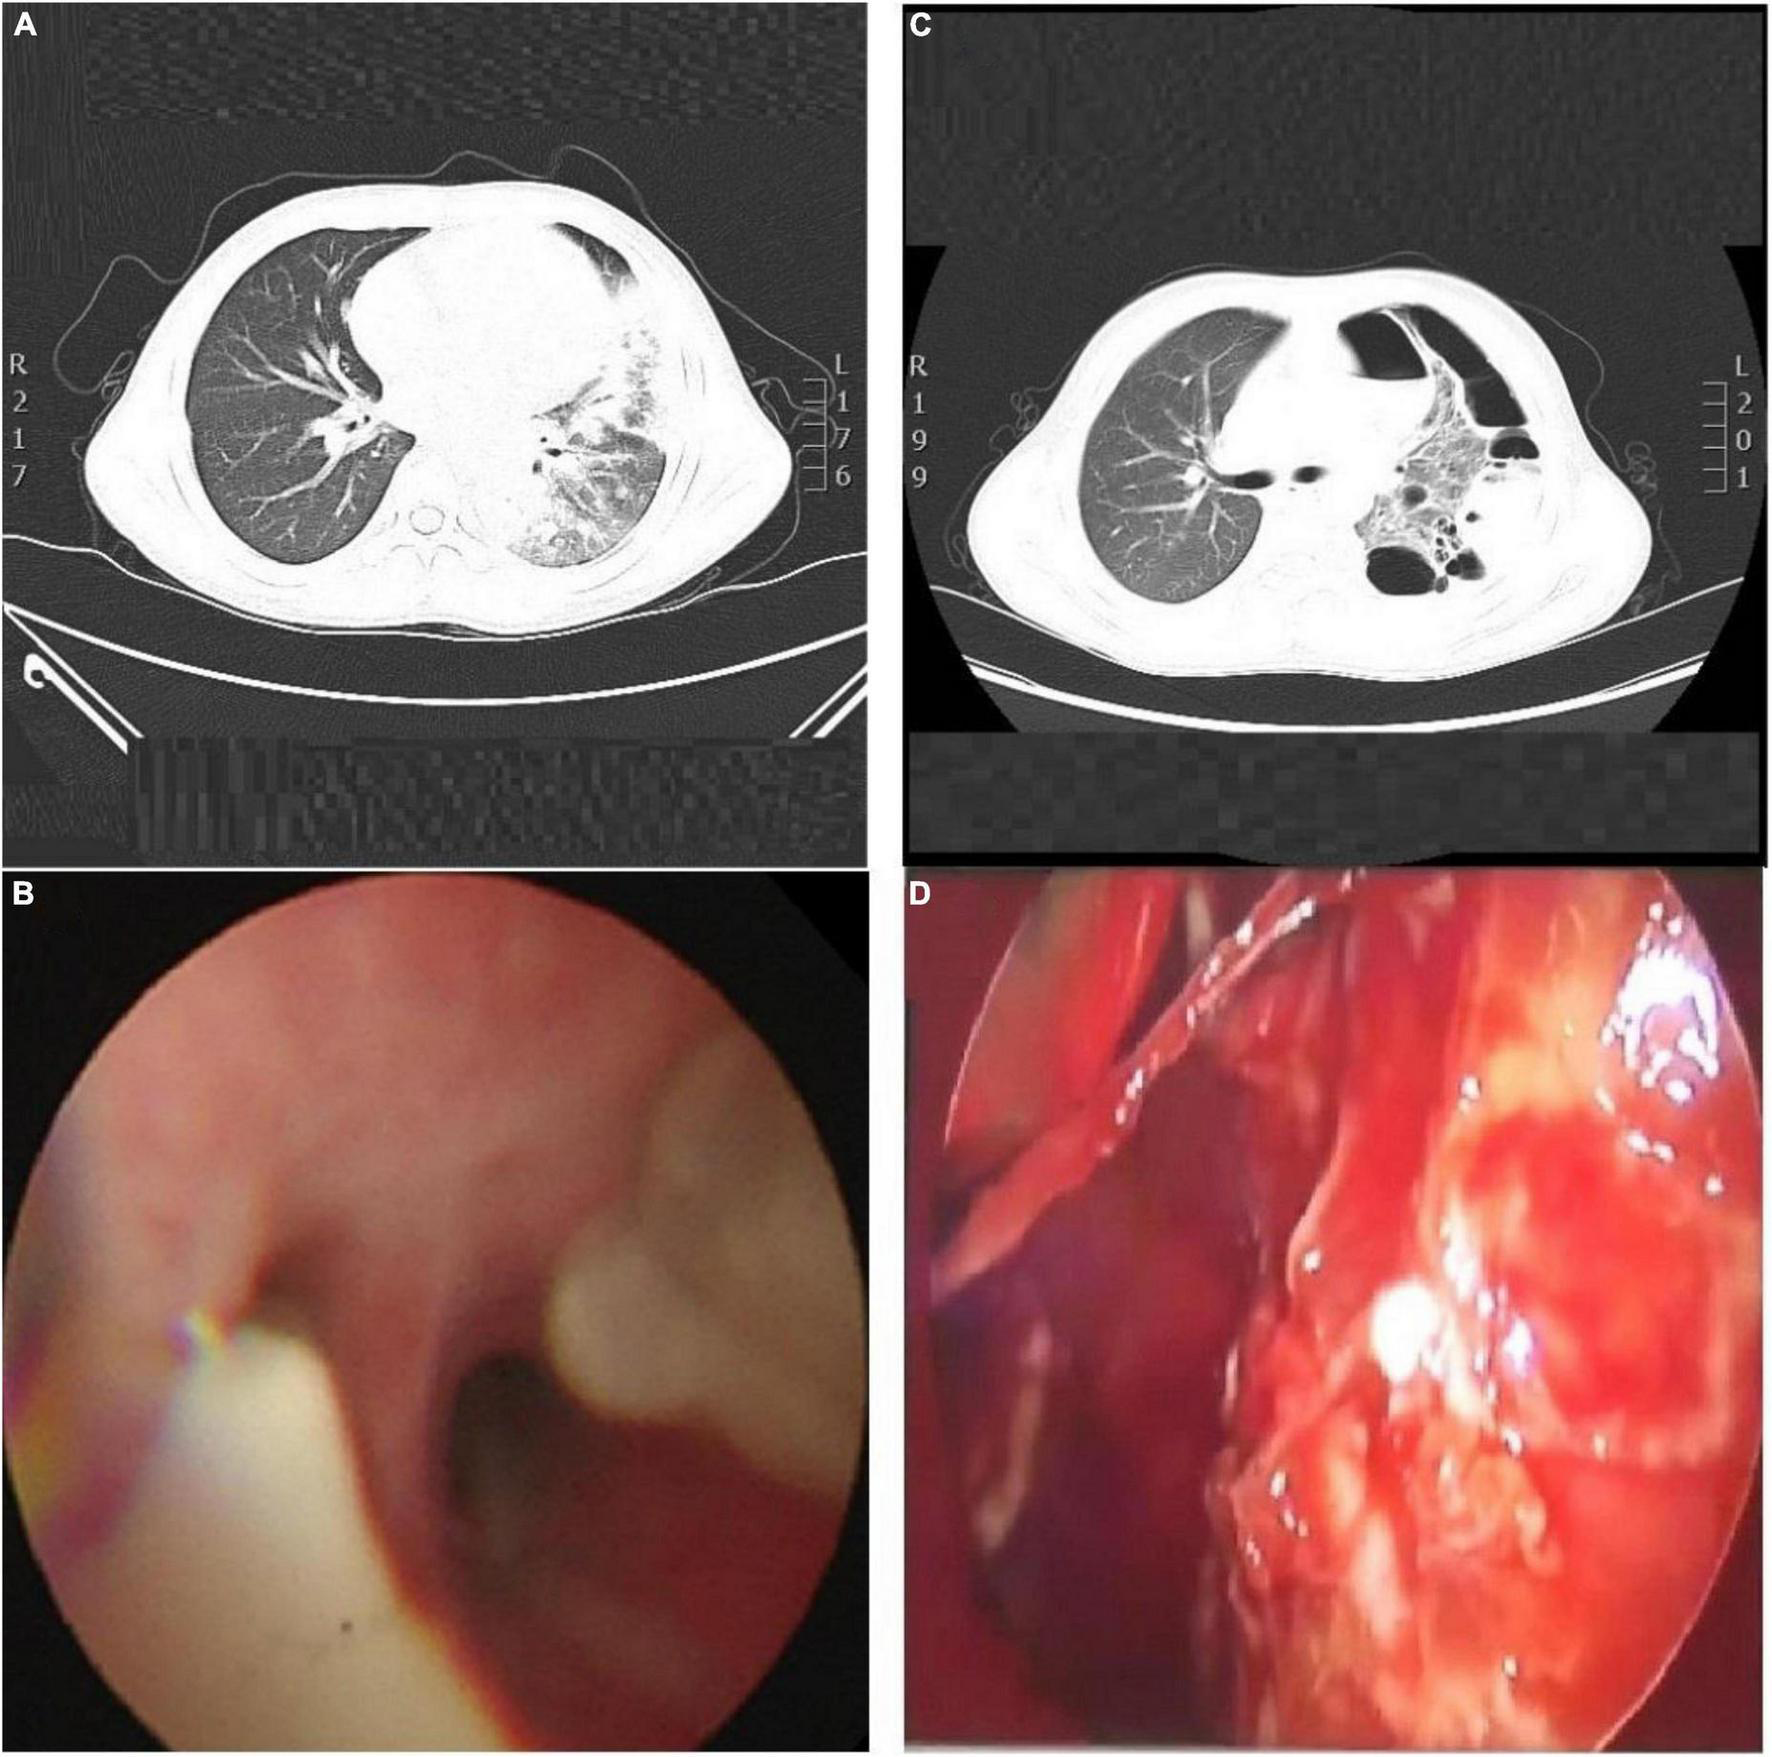

A previously healthy 13-year-old boy was hospitalized with a three-day history of cough and fever. He was diagnosed with IAV infection in the local hospital. On admission, he was in respiratory distress and complained of left-sided chest pain. Laboratory indicators were shown in Table 1. His oxygen saturation level was 89–94% with an oxygen supply and he could not even lie down. The computed tomography (CT) scan of his chest showed atelectasis and a small amount of pleural effusion (Figure 1A). He was provided with oxygen support, anti-infection therapy and nutritional support. A diagrammatic representation of the treatment and outcome was presented in Figure 2.

FIGURE 1

(A) CT scan of his chest, show the left lung and the right lower lobe consolidation, with atelectasis in the lower lobe of the left lung. The left pleural cavity showed a small amount of pleural effusion, and the lumen of the bronchial branch of the left lower lobe was not unobstructed. (B) Bronchoscopy, show the basal segment of left lower lobe, the bronchial mucosa was rough, a large number of yellow and white mucus plugs were found in the opening, and the ventilation was not smooth. (C) Chest CT scan. Indicate consolidation of left and right upper and lower lobes with signs of atelectasis and multiple cavities in the left lung, partially wrapped left pneumothorax. (D) Thoracoscopy, show the lung surface covered with a yellow purulent moss-like layer.

The following day, the patient was not doing well and developed a stridor; hence, the decision was made to perform a flexible bronchoscopy with bronchoalveolar lavage (BAL) under ECG monitoring and respiratory oxygen support after employing local anesthesia (Figure 1B). Because the patient’s severe pneumonia progressed rapidly and even endangered his life, an early and accurate etiological diagnosis was very important for the implementation of pathogen-specific treatment. Therefore, the next-generation sequencing analysis from BAL fluid was performed, and it indicated S. aureus as the infectious pathogen residing in the patient’s lungs. Blood culture for microbial infection was also found positive for S. aureus. On the fourth day of hospitalization, the chest X-ray showed no improvement, so the bronchoscope was continued to be used for BAL. Tracheal aspirate showed heavy growth of MRSA sensitive to linezolid, vancomycin, and rifampicin. Meanwhile, it was resistant to tetracyclines and quinolones.

Unfortunately, the patient was very ill, remained pyrexial (38.8°C) and developed a left-sided pyopneumothorax on day 8 of hospitalization with recurring fever, and the body temperature increased to 38.8°C. The patient complained of chest pain related to breathing abnormality, accompanied by apparent breath-holding. B-scan ultrasound and CT imaging (Figure 1C) of thorax revealed massive bilateral pleural effusions and multiple cavities in the left lung. Based on the laboratory and imaging diagnostic investigations, thoracentesis was performed on the patient’s left chest, and the chest tube was placed on the same side.

Even after 12 days of hospitalization and treatment, the patient’s condition did not improve due to poor drainage of empyema as a result of cellulose and thick pus accumulation. The patient underwent thoracoscopy to diagnose and treat pleural effusion (Figure 1D). After thoracoscopic investigations of the pleural cavity, the lung surface was cleared of the thick yellow moss-like layer of pus, and the left chest cavity was repeatedly flushed until the outflow was clear. At the end of the surgical procedure, the light bloody liquid could be seen in the chest bottle, and the chest tube was connected to the closed thoracic drainage system to prevent further pleural effusions.